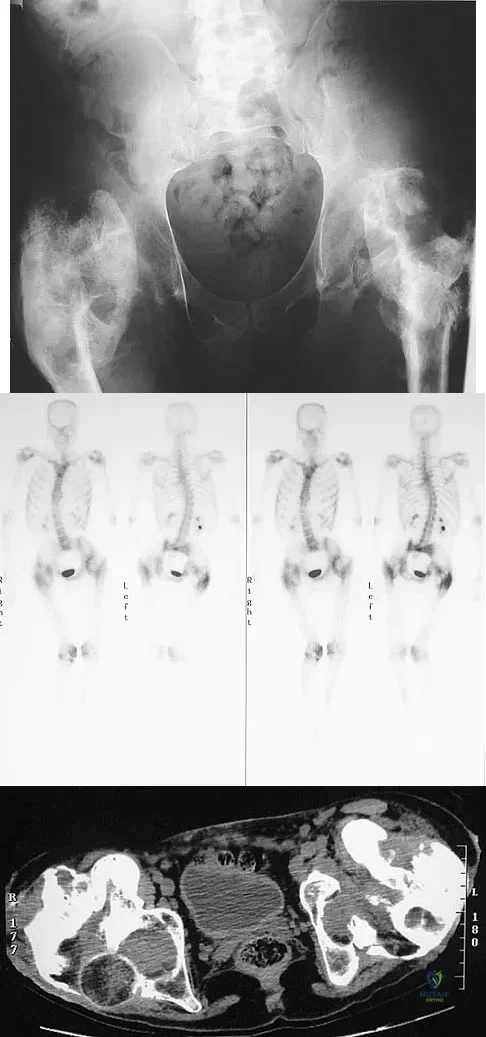

The lesion seen in Figure 4 is most likely the result of metastases from what solid organ?

Figure 11a shows the AP pelvis radiograph of a 25-year-old man who sustained a spinal cord injury 10 years ago. A bone scan and a CT scan are shown in Figures 11b and 11c. To prevent recurrence after resection, management should consist of